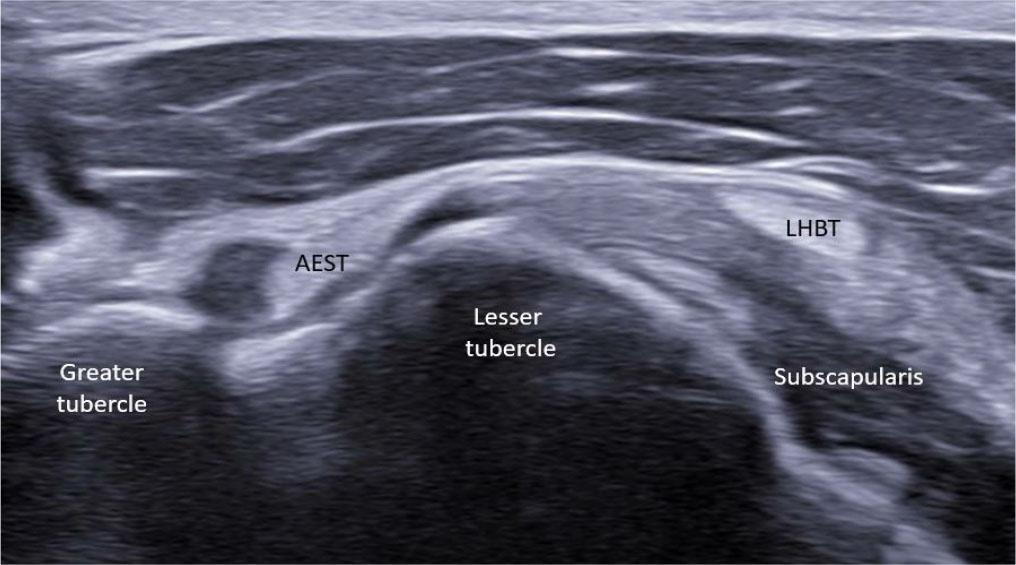

Ultrasound image showing normal aponeurotic expansion of supraspinatus tendon (AEST) anterolateral to the long head of the biceps tendon (LHBT) at the intertubercular groove

At the level of the rotator interval, AEST was assessed for echogenicity, intrasubstance tears, and its relationship to the LHBT and subscapularis tendon (Fig. 3), while the supraspinatus was checked for tear-related changes. AEST was then examined at the intertubercular groove to determine its position (intragroove, subluxation, dislocation, medial dislocation; Fig. 4), along with LHBT and subscapularis integrity. The remaining shoulder structures, including the other rotator cuff tendons and the glenohumeral and acromioclavicular joints, were systematically reviewed. The findings are summarized in Tab. 1.